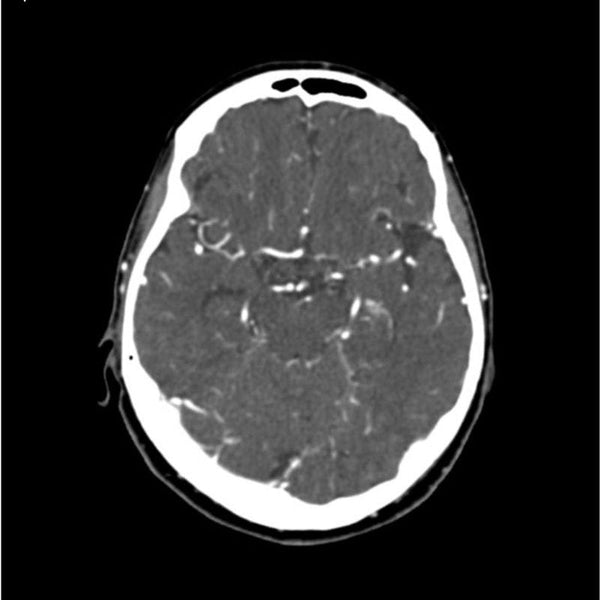

1/4oz Balloon Fiesta Round - $862 Venmo, Zelle or Mailed。Contrast-enhanced computed tomography (CT) of the neck。HJ Balloon&Co (@balloon_nco) · Mystic, CT。ご覧いただきありがとうございます。Krazy 8 Balloons。OMMOのNECK GATHER BALLOON CTネックギャザーバルーンコートです。Tina:jojun ティーナジョジュン フェイクスエード ショートジャケット。色はモカ、サイズは36です。ザ・ノース・フェイス ダウンコート ストレートブラウン Mサイズ。数回着用しました。バックサテンダブルブレストジャケット ベージュ。2023awの完売商品です。バーバリーブリット ダウンコート Lサイズ ノバチェック ブルーフォックスファー。軽くて温かいので、これから大活躍してくれると思います!素人の自宅保管品で完璧ではありませんので、ご理解いただける方にお願いいたします!バルーン型がとても可愛いです。ドルガバ ジャケット。